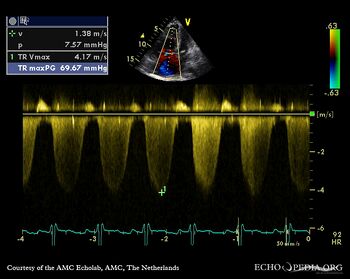

| Courtesy of: AMC Echolab, AMC, The Netherlands | |

| A4CH with Color Doppler: severe tricuspid regurgitation | Continuous-wave Doppler signal of tricuspid regurgitation, pulmonary hypertension |